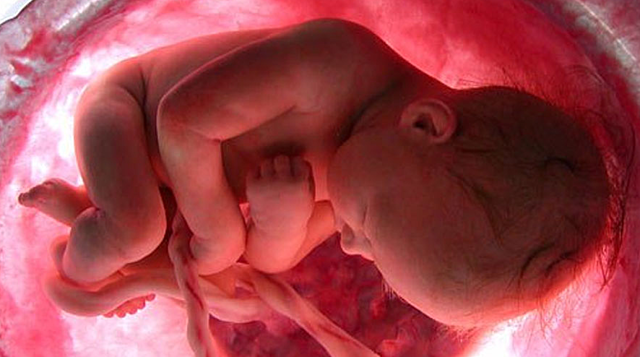

El bebe ya pesa unos 1.350 gramos y mide unos 38 centímetros de la cabeza a los pies con 30 semanas de embarazo. Si todo transcurre con normalidad, la futura madre tendra que ir al ginecólogo hasta la semana 36 de embarazo, ya que las citas se dan cada cuatro o seis semanas.

En la semana 31 de embarazo, pesa entre 1.600 y 1.700 gramos aproximadamente y mide alrededor de 41-42 centímetros. Alrededor de la semana 31 de gestación, los bebés suelen colocarse ya en posición cefálica, la más idónea para nacer y si eso ocurre notarás ya sus movimientos en la parte alta del abdomen.

El bebé pesa en la semana 32 de embarazo entre 1,8 y 2 kilos aproximadamente, y mide entre 38 y 43 centímetros. Ahora se cree que el bebé dentro del útero puede pensar, e incluso crear su primer recuerdo a partir de la semana 32.

En la semana 33 de gestación,mide unos 43-45 cm y pesa cerca de 2.000 gramos. El cerebro del bebé sigue desarrollándose y ahora ya tiene los cinco sentidos preparados para cuando baya que nacer.

El bebé mide aproximadamente 46 centímetros y pesa alrededor de 2,200 gramos. Sus pulmones ya están casi completamente formados y sus huesos se han ido endureciendo pero todavía son muy flexibles, incluidos los de la cabeza.Su cráneo todavía no está completamente cerrado, lo cual le permite adaptarse con mayor facilidad al canal de parto en el momento de nacer. Por eso, algunos bebé nacen con la cabeza en forma de cono o aplastada, pero esto se revierte a los pocos días de nacer.

Los pulmones del bebé acaban su proceso de maduración. Pero se debe estar pendiente de signos de parto prematuro (contracciones , sangrado vaginal o rotura prematura de membranas) porque todavía es pronto para dar a luz. Notarás mucha presión del bebé en la pelvis y la vulva e incluso calambres en la vagina. El bebé pesa unos 2.500 gramos y mide alrededor de 45 centímetros en la semana 35 de embarazo. A partir de ahora, los pulmones del bebe ya están maduros.

En estas semanas el bebé pesa unos 2.750 gramos y mide 46 centímetros . En estas semanas de gestación todavía se le considera un feto prematuro. El bebé sigue moviéndose, lo notarás a diario, pero es raro que logre darse la vuelta dentro del útero materno.

En estas semanas de gestación deben estar muy atenta a las contracciones de parto.En estas semanas del embarazo empieza la cuenta regresiva hasta la meta del embarazo que es el momento del parto

El bebé en la semana 40 de embarazo mide entre 48 y 51 centímetros de la coronilla a las nalgas, y el peso se sitúa alrededor de los 3500 gramos.Lo que está claro es que, cuanto más nos alejemos de la fecha prevista del parto, más probable es que el bebé pese más.